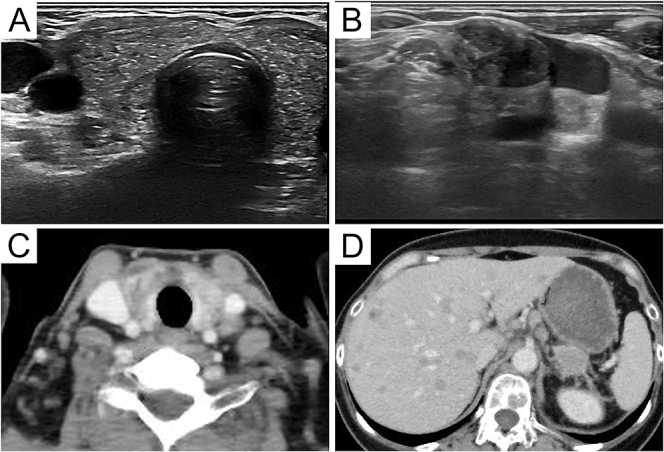

Summary: A 56-year-old woman with cervical pain with a history of ovarian clear cell carcinoma stage IIIC was admitted to a primary care doctor. Ultrasonography revealed a microhyperechoic nodule in the thyroid gland and cervical lymph node enlargement, and fine-needle aspiration was performed. The results showed malignancy, and she was admitted to our hospital. The differential diagnoses included primary thyroid neoplasms and thyroid metastases from ovarian clear cell carcinoma. A needle biopsy of the thyroid gland was performed. Immunohistochemistry revealed that the tumor cells were positive for cytokeratin AE1/AE3, hepatocyte nuclear factor-1-beta and PAX8 and negative for thyroglobulin and thyroid transcription factor-1. Therefore, we diagnosed the patient with thyroid metastasis from ovarian clear cell carcinoma. There were no compressive symptoms at the time of the visit to our hospital, and surgery was considered unnecessary. Systemic treatment for ovarian clear cell carcinoma was continued. Three months later, she died of a stroke due to Trousseau's syndrome.

Learning points: Metastasis of ovarian carcinoma to the thyroid gland is extremely rare.Using histology and immunostaining, we were able to accurately diagnose thyroid metastasis of ovarian clear cell carcinoma.